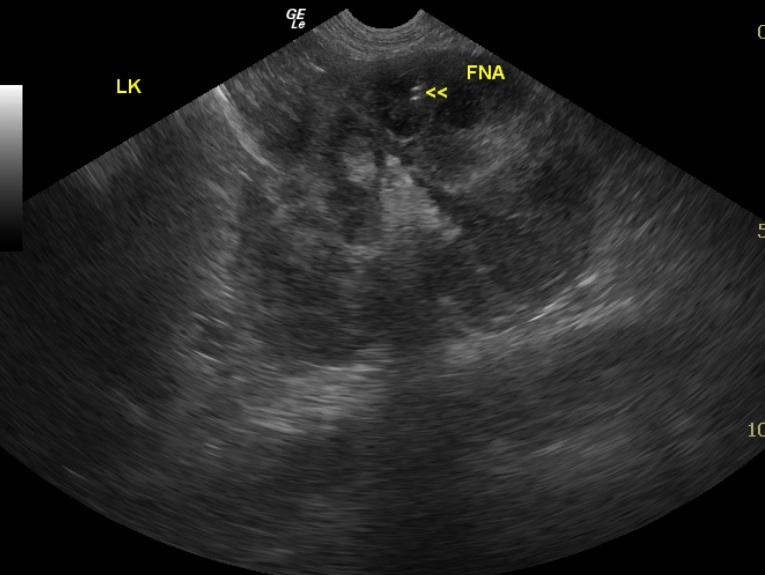

Ultrasound-guided fine needle aspirates of the left kidney were performed. Cytology revealed malignant lymphoma. The cell morphology suggested intermediate to high grade B-cell lymphoma.

The kidneys revealed severe renomegaly (8 cm each) with multiple target type hypoechoic lesions. Round cell neoplasia is suspected. No evidence of acute or chronic inflammatory or infarctual changes were noted.

Likely bilateral renal neoplasia such as lymphoma or other round cell disease.